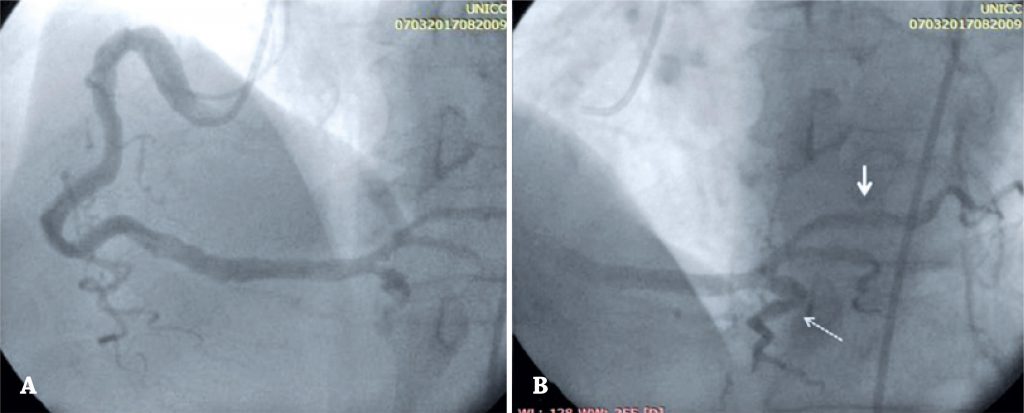

Quando os stents são implantados em ambiente trombótico, podem provocar embolia coronária, aumentando o risco de no-reflow e complicações clínicas. O objetivo deste estudo foi avaliar o impacto de adiar o implante do stent em pacientes com síndromes coronárias agudas e artérias coronárias com alta carga de trombos, usando o anticoagulante oral direto apixabana em combinação com a terapia antiplaquetária dupla.

Foram incluídos 11 pacientes consecutivos. Após a primeira coronariografia, os pacientes receberam tratamento com aspirina, clopidogrel e apixabana por 7 dias. Outra angiografia/intervenção foi planejada, e o stent foi implantado em casos com diâmetro de estenose residual >30%.

A maioria dos participantes era do sexo masculino (80%). Todos eram diabéticos. Doença multiarterial foi detectada em 20% dos casos. Todos os pacientes permaneceram clinicamente estáveis entre o primeiro e o segundo procedimento. Não foi necessário implantar stent em dois pacientes. Nos nove restantes, a estenose residual média e a carga de trombo foram visualmente menores, tendo sido implantado stent farmacológico. Não houve fenômeno de no-reflow ou slow-flow após a implantação do stent, com blush miocárdico grau 3 em todos eles.